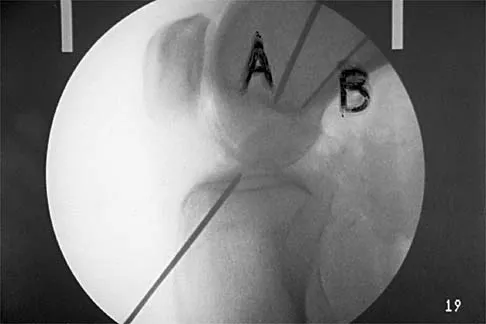

Question 87

Figure 16 shows the lateral radiograph of a patient who is scheduled to undergo an anterior cruciate ligament (ACL) reconstruction. If the graft is tensioned at 20 degrees of flexion and the femoral tunnel is created by passing a reamer over the guide wire marked "A," the resulting ligament reconstruction will excessively

Explanation